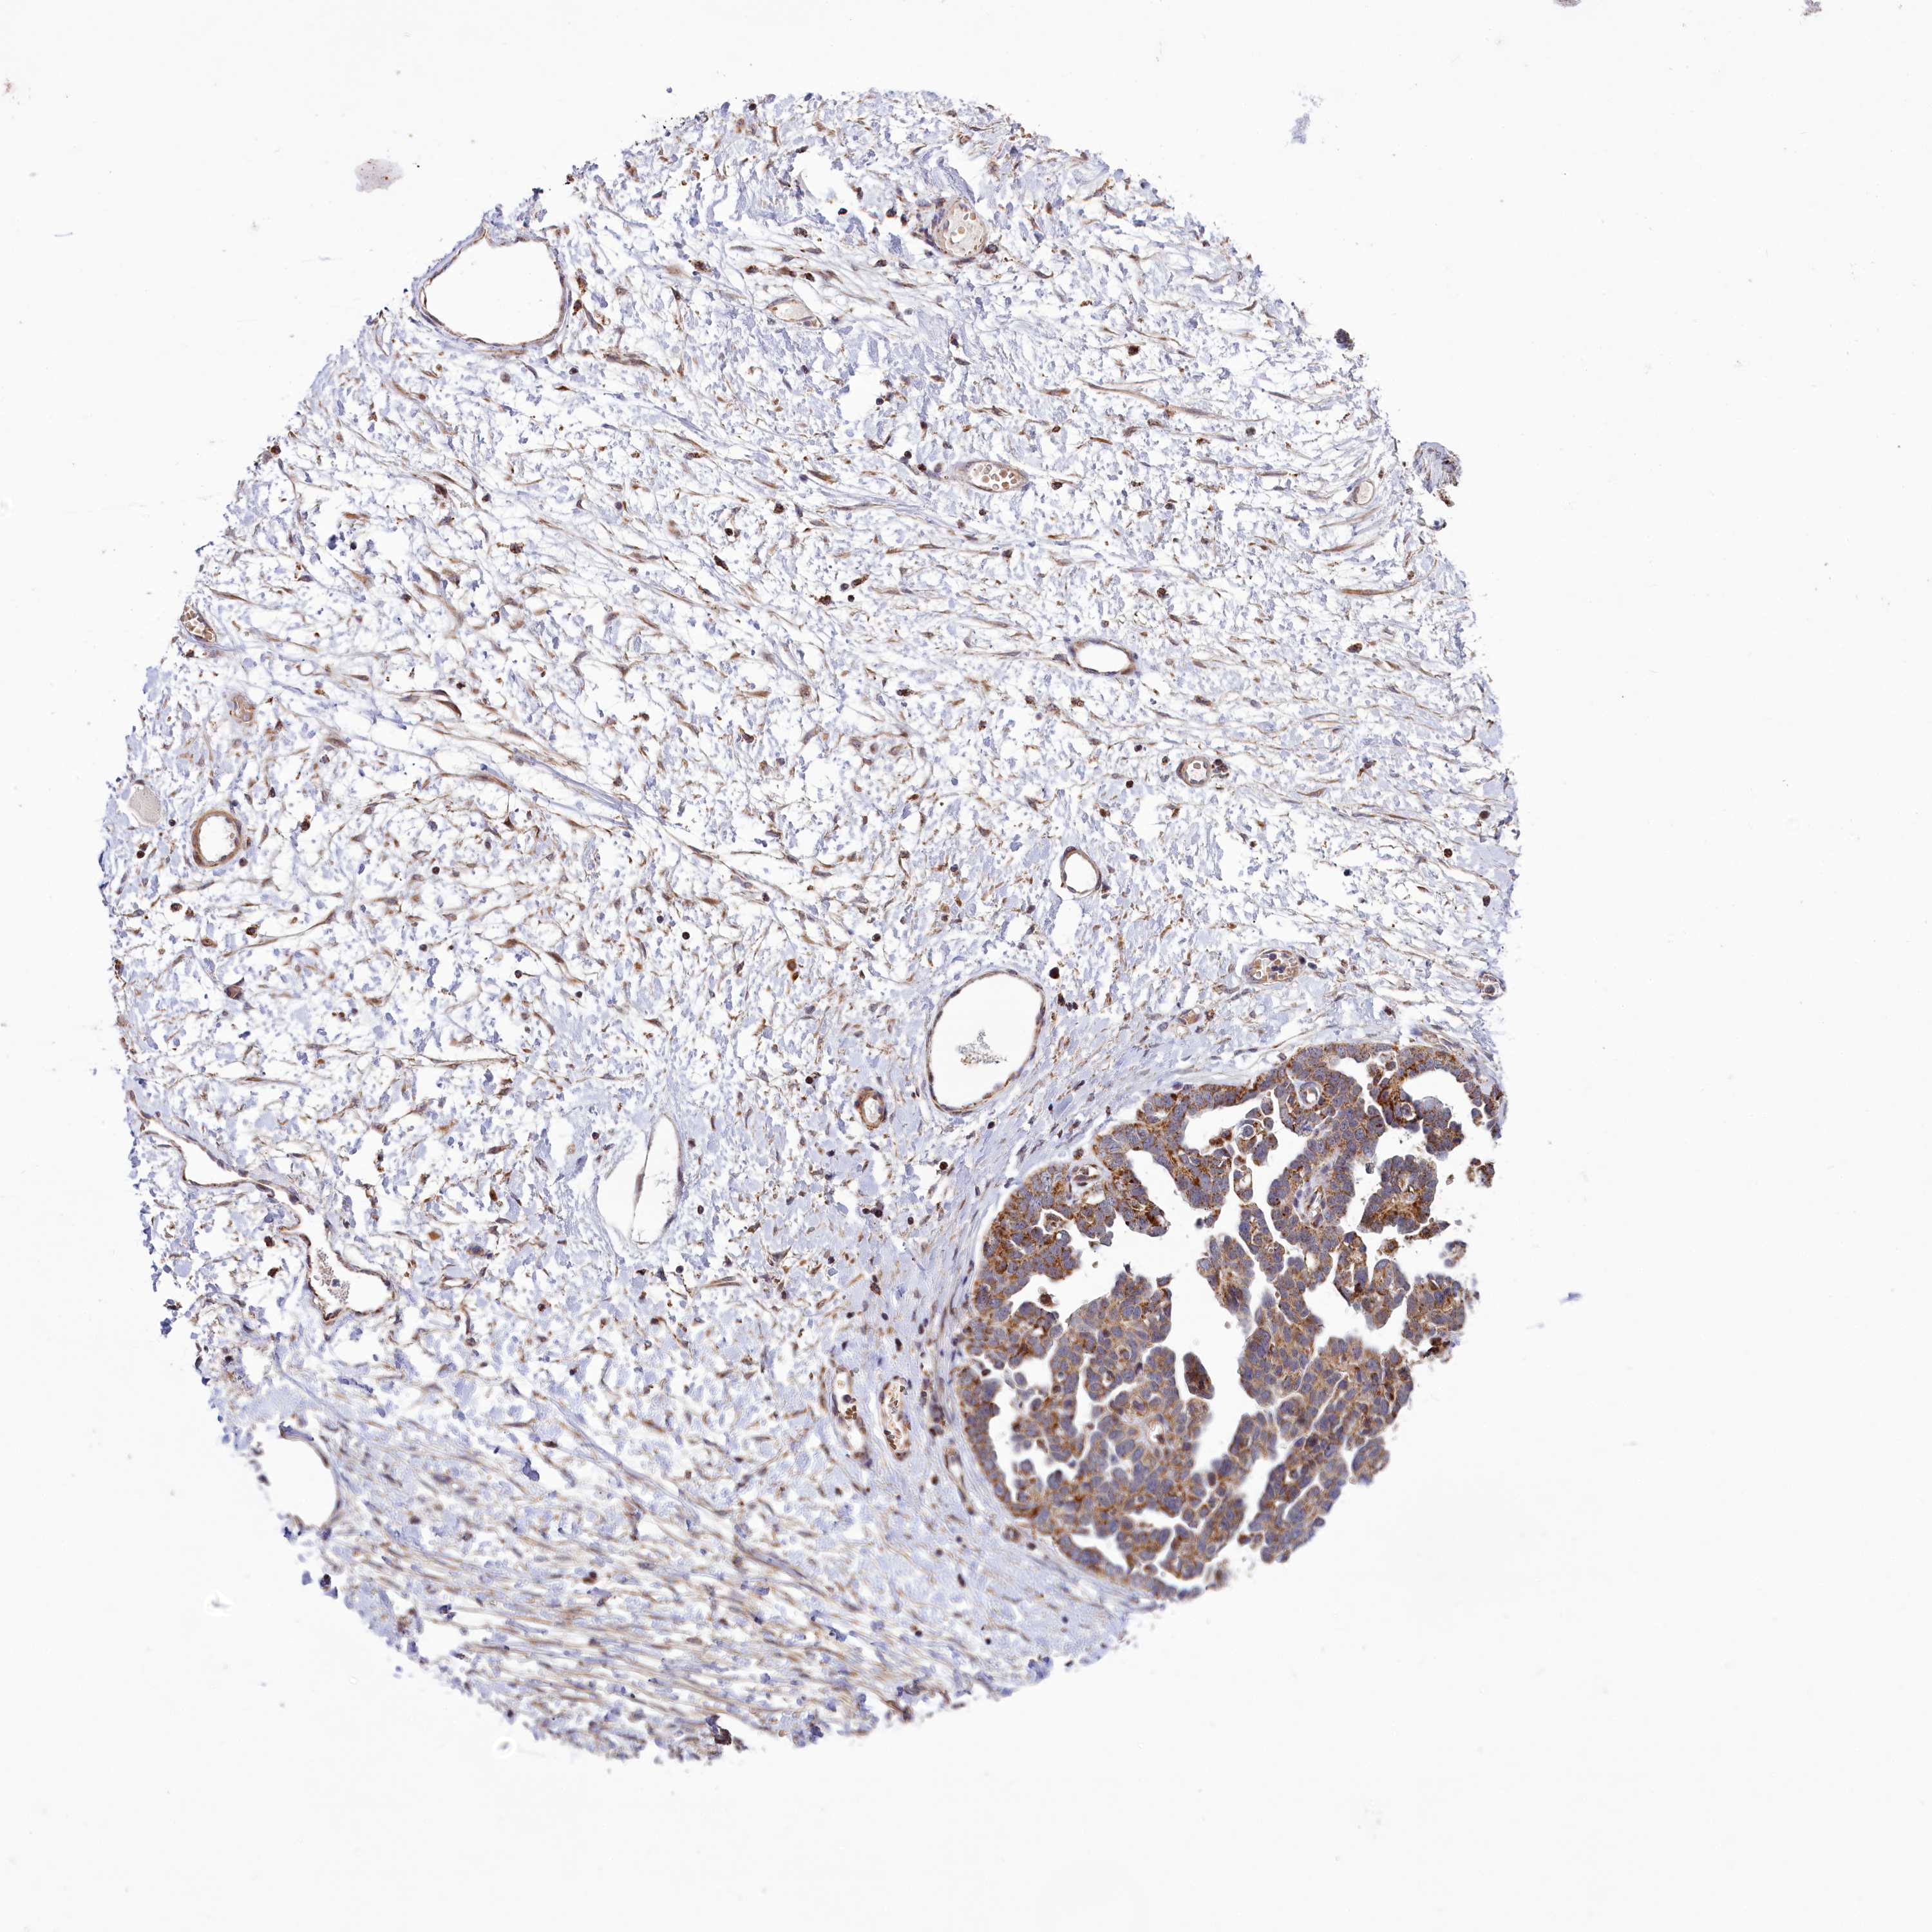

OVARIAN CANCER - Protein expressioni

A mouse-over function shows sample information and annotation data. Click on an image to view it in a full screen mode. Samples can be filtered based on level of antibody staining by selecting one or several of the following categories: high, medium, low and not detected. The assay and annotation is described here.

Note that samples used for immunohistochemistry by the Human Protein Atlas do not correspond to samples in the TCGA dataset.

Antibody stainingi

Antibody staining in the annotated cell types in the current human tissue is reported as not detected, low, medium, or high, based on conventional immunohistochemistry profiling in selected tissues. This score is based on the combination of the staining intensity and fraction of stained cells.

Each image is clickable and will lead to virtual microscopy that enables deeper exploration of all samples and also displays staining intensity scores, fraction scores and subcellular localization as well as patient and tissue information for each sample.

Antibody HPA039016

Carcinoma, endometroid

Cystadenocarcinoma, mucinous, NOS

Carcinoma, NOS

Cystadenocarcinoma, serous, NOS